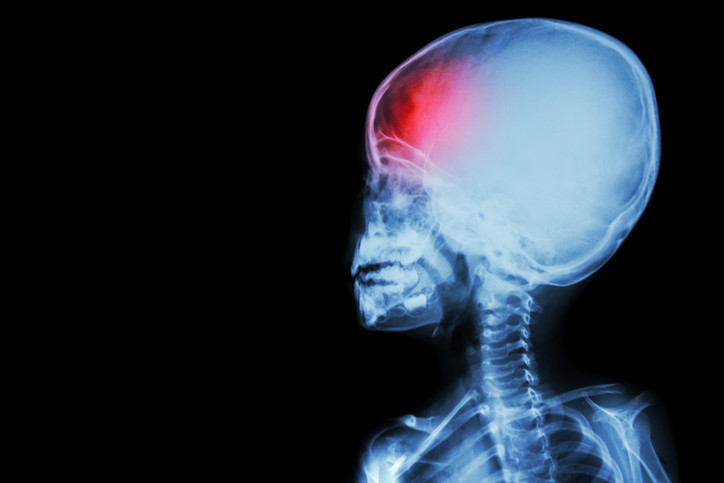

Son yıllarda yapılan araştırmalar, kan gruplarının yalnızca bağışıklık sistemi ve kan pıhtılaşmasıyla değil, aynı zamanda felç riski gibi hastalıklarla da bağlantılı olabileceğini gösteriyor.

ABD’de Maryland Üniversitesi’nde gerçekleştirilen çalışmada, A kan grubuna sahip kişilerin, iskemik inme (beyne giden damarların tıkanması) geçirme olasılığının daha yüksek olduğu, 0 kan grubuna sahip bireylerin ise daha düşük risk taşıdığı tespit edildi. Bu çalışma, genetik faktörlerin felç riski üzerindeki rolünü anlamak adına önemli bir adım olarak görülüyor.

İnme, genellikle 65 yaş ve üzeri yetişkinlerde daha yaygın olsa da genç yetişkinler arasında da artan bir oranda görülüyor. Örneğin ABD’de 20-44 yaş arasındaki yetişkinlerde iskemik inme oranı, 1993’te 100 binde 17 iken 2015'te 100 binde 28’e yükseldi. Genç yetişkinler arasında inme kaynaklı ölüm riski de artıyor.